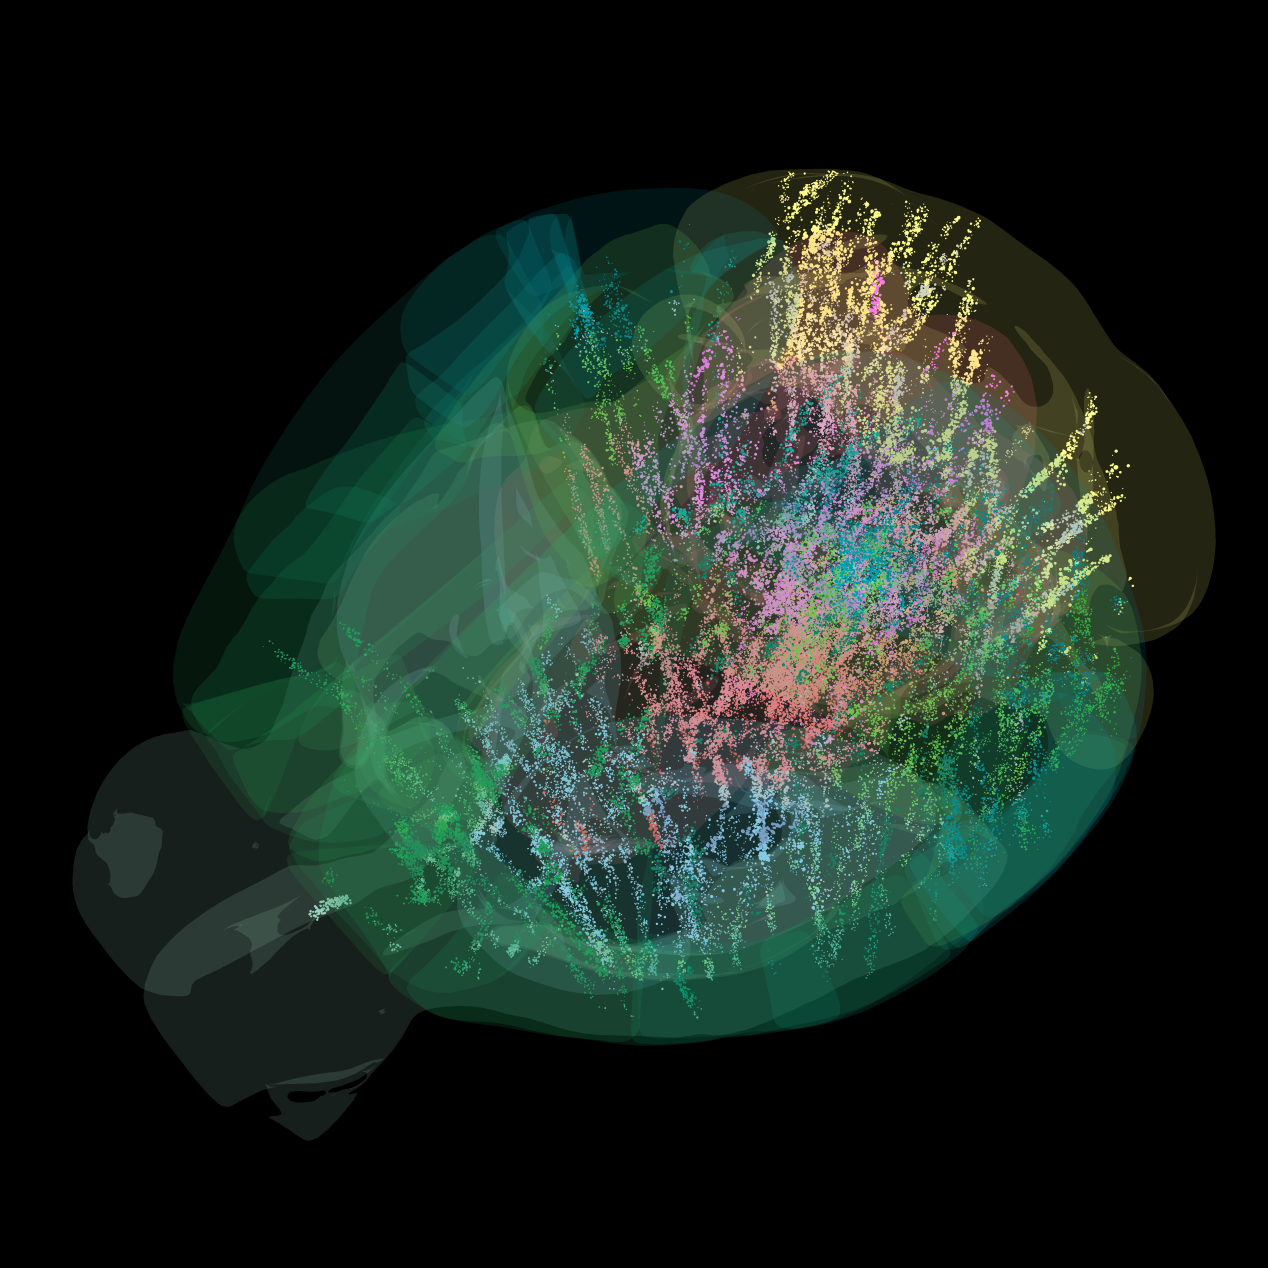

首張完整動(dòng)物大腦活動(dòng)圖譜發(fā)布

2025-09-09 01:01:00